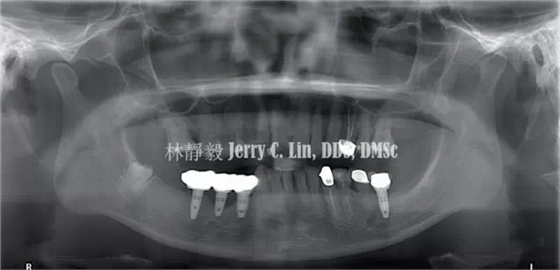

案例在植牙治療完成兩年后,45位置的植體發(fā)生種植體周圍炎(peri-implantitis)如圖1、圖2,約有9個螺紋處的齒槽骨遭到破壞。

QQ圖片20150710145056.png圖1 曲面體層片可見45位置發(fā)生種植體周圍炎

術(shù)后曲面體層片仍可明顯看出牙槽骨破壞的型態(tài)(圖9),此乃因FDBA在骨再生之前顯示透光度較低,藉此追蹤X光上的骨質(zhì)變化,有助于將來判斷骨再生的真實性。

QQ圖片20150710150018.png圖9 曲面體層片可見牙槽骨破壞

術(shù)后半年進行復查,X線片(圖15、圖16)顯示骨再生已達第一螺紋,種植牙周圍約有8~9個螺紋的牙槽骨獲得再生,同時也解決了種植體周圍炎的問題。

圖15 術(shù)后半年曲面體層

圖16 術(shù)后半年根尖片